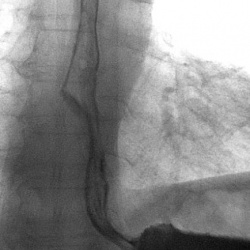

Мужчина 60 лет. Дисфагия. Боль при глотании. Эндоскопически - резкое сужение входа в пищевод, пройти не удалось.